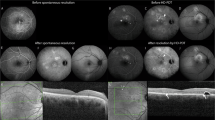

Thirteen consecutive eyes of 12 patients for whom fundus near-infrared fluorescence and 20° retinal sectional images were obtained using HRA2 and Spectralis OCT, respectively, 5 days after vitrectomy combined with ICG-assisted inner limiting membrane peeling for DMO. The relationship between the characteristics of the ICG hyperfluorescence and the cystoid spaces in the outer plexiform layer (OPL) on SD-OCT images was evaluated.

A total of 390 well-demarcated areas of ICG hyperfluorescence were delineated on 20° radial OCT scans dissecting the fovea 5 days after vitrectomy. The areas of ICG hyperfluorescence in the parafovea or perifovea were significantly smaller than those at the fovea. Most areas of hyperfluorescence were irregularly shaped in the parafovea and perifovea, whereas 18 of 38 areas of hyperfluorescence were round or oval at the fovea (P<0.001). SD-OCT delineated the cystoid spaces in the OPL in 73 areas of hyperfluorescence that were round or oval and accompanied by dark spots more frequently than that without cystoid spaces on OCT images (P<0.001 and P=0.002). Of the 123 cystoid spaces in the OPL on OCT images, 44 did not have ICG hyperfluorescence, had lower OCT reflectivity, and contained fewer hyperreflective foci than those with ICG hyperfluorescence (P<0.001 and P=0.020).